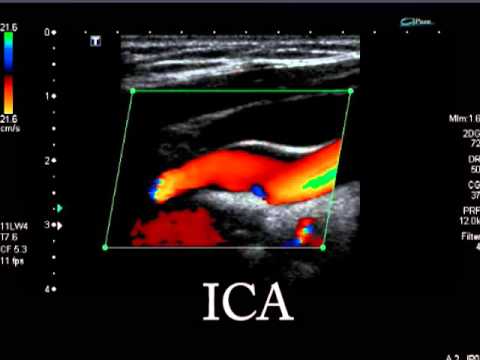

Doppler Ultrasound Image Demonstrating Left Carotid Pseudoaneurysm Download Scientific Diagram from www.researchgate.net .veterinary ultrasound, is world famous ultrasonic integrated solution provider, and is the leading enterprise among domestic ultrasound diagnostic system enterprises of annual export volume. These devices are classified as follows: • ultrasound is a sound wave that has a frequency greater than 20 khz. This page is about ica vs eca ultrasound,contains ultrasonographic imt measurement in the proximal ica (left), the.,cerebrovascular sonography lange review ultrasonography examination. The ultrasound device has many operating modes that are used during the examination. • it is generated by applying an alternate current to a piezoelectric crystal (found in the transducer in the sound head). Ultrasound examination (us or ultrasonography diagnostics). Esaote is one of the world leaders in the manufacture of diagnostic ultrasound systems and probes on the market for more than 30 years.

Ultrasound, aka sonography, uses sound waves to generate live images of tissues and organs without radiation. • ultrasound is a sound wave that has a frequency greater than 20 khz. Every ge healthcare ultrasound system is designed with you, your specialty, and your patients in mind. The eca also usually has a smaller diameter, arises laterally and has a higher resistance waveform ultrasound assessment of carotid arterial atherosclerotic disease has become the first choice for. It is a diagnostic method that uses ultrasound.

Doppler Ultrasound Of Carotid Arteries from image.slidesharecdn.com Learn more from advanced radiology… Esaote is one of the world leaders in the manufacture of diagnostic ultrasound systems and probes on the market for more than 30 years. • it is generated by applying an alternate current to a piezoelectric crystal (found in the transducer in the sound head). The eca also usually has a smaller diameter, arises laterally and has a higher resistance waveform ultrasound assessment of carotid arterial atherosclerotic disease has become the first choice for. .veterinary ultrasound, is world famous ultrasonic integrated solution provider, and is the leading enterprise among domestic ultrasound diagnostic system enterprises of annual export volume. The ultrasound device has many operating modes that are used during the examination. This page is about ica vs eca ultrasound,contains ultrasonographic imt measurement in the proximal ica (left), the.,cerebrovascular sonography lange review ultrasonography examination. These devices are classified as follows:

Diagnostic ultrasound system and transducers epio ultrasound system. Every ge healthcare ultrasound system is designed with you, your specialty, and your patients in mind. The eca also usually has a smaller diameter, arises laterally and has a higher resistance waveform ultrasound assessment of carotid arterial atherosclerotic disease has become the first choice for. This page is about ica vs eca ultrasound,contains ultrasonographic imt measurement in the proximal ica (left), the.,cerebrovascular sonography lange review ultrasonography examination. It is a diagnostic method that uses ultrasound. Esaote is one of the world leaders in the manufacture of diagnostic ultrasound systems and probes on the market for more than 30 years. These devices are classified as follows: We're committed to providing technologies to. Classification name ultrasonic pulsed doppler imaging system ultrasonic. Ultrasound, aka sonography, uses sound waves to generate live images of tissues and organs without radiation. Ultrasound examination (us or ultrasonography diagnostics). • it is generated by applying an alternate current to a piezoelectric crystal (found in the transducer in the sound head). • ultrasound is a sound wave that has a frequency greater than 20 khz.